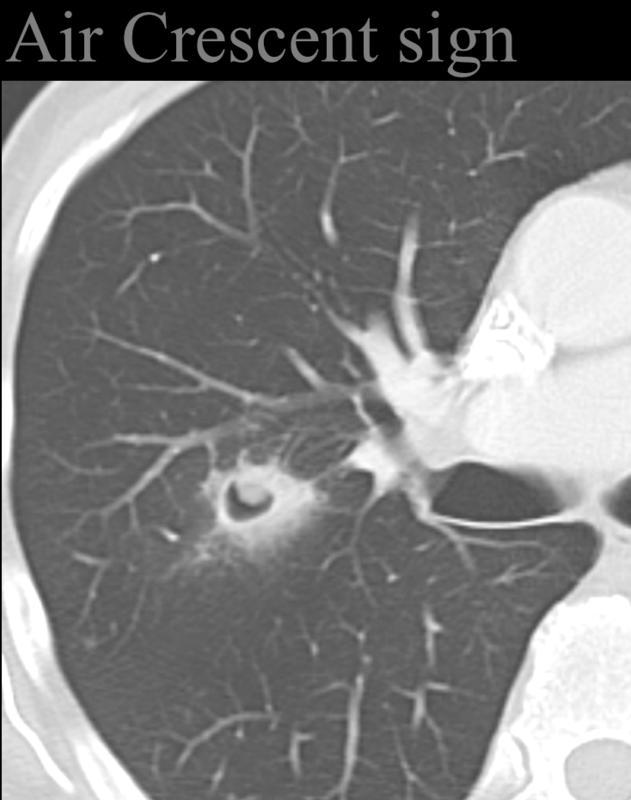

Air crescent sign

invasive aspergillosis